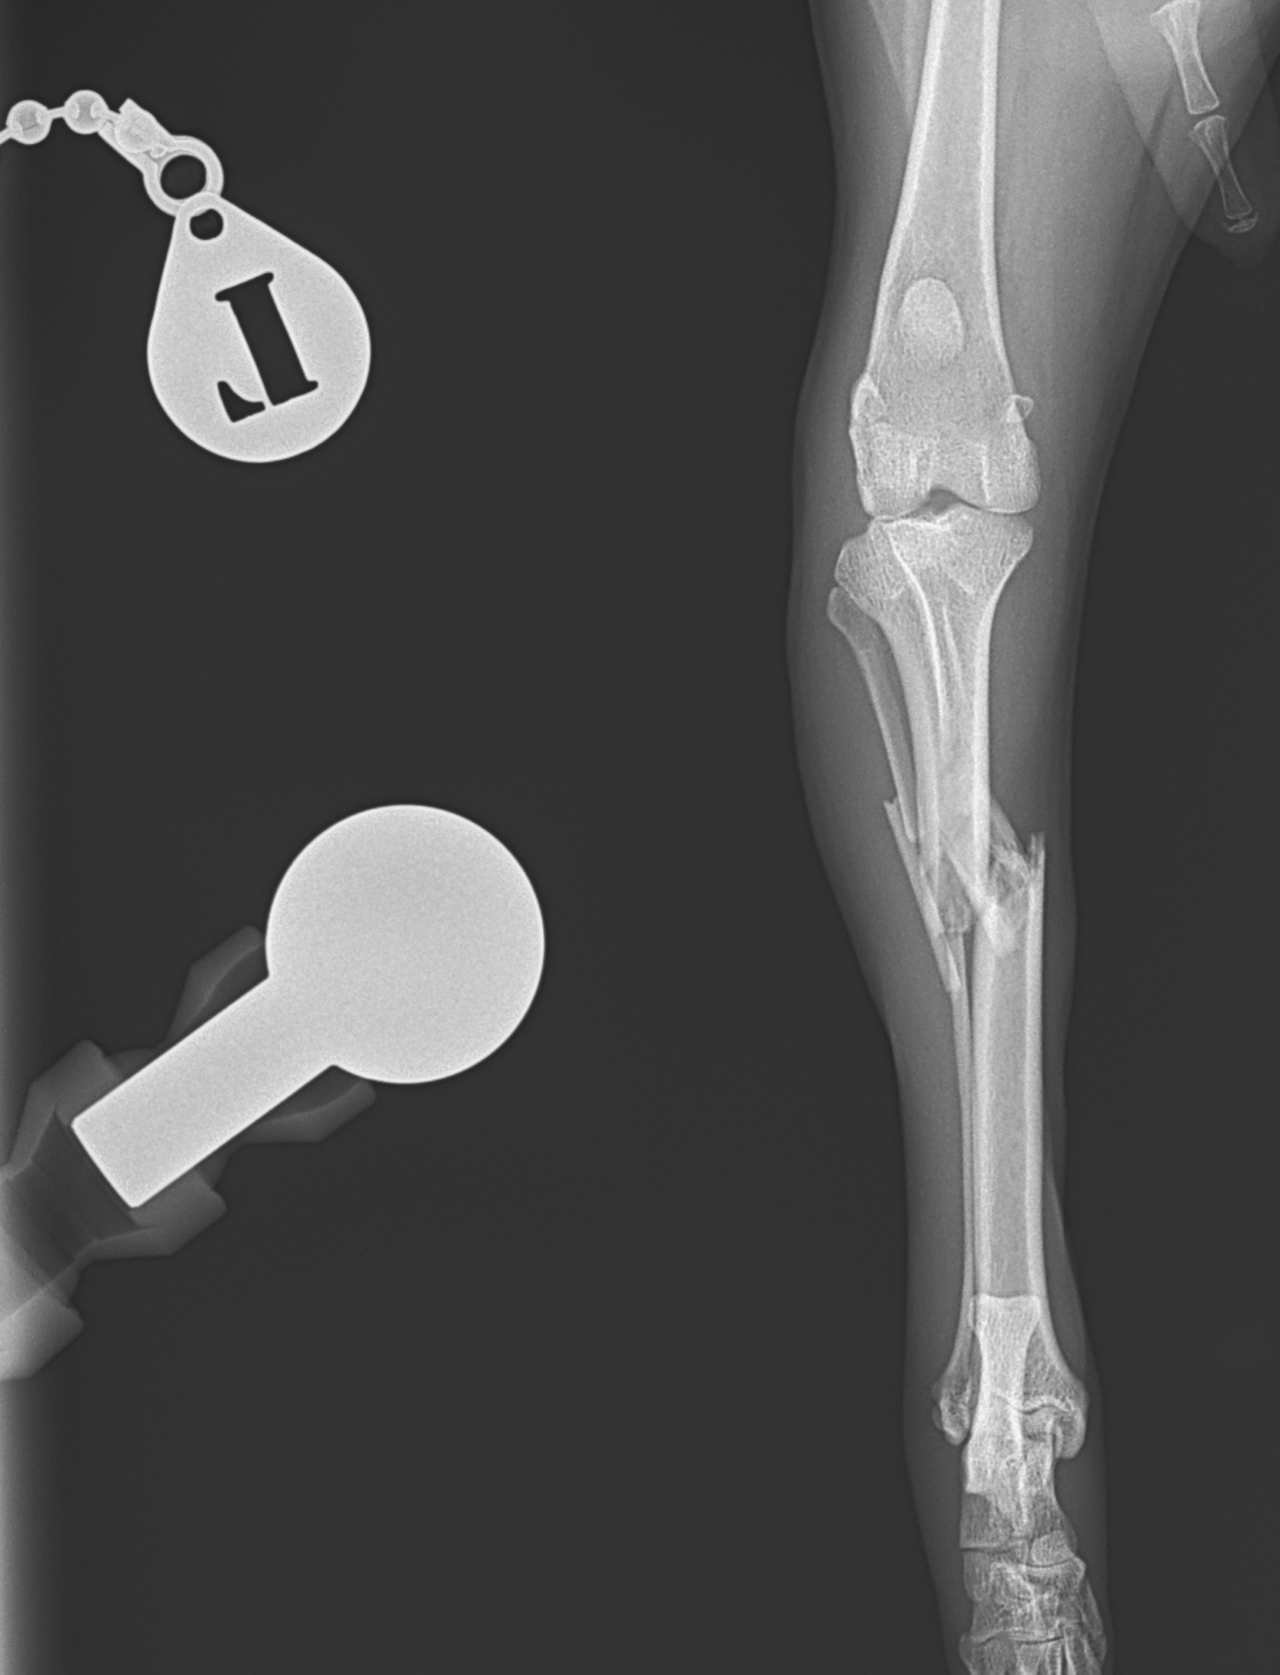

脛骨粉砕骨折

13歳のトイ・プードルがソファーからジャンプした際に後肢を傷めて救急病院を受診されました。エックス線検査で脛骨近位部の粉砕骨折(comminuted tibial fracture)が確定され、骨固定術の依頼がありました。小型犬では、ソファーやベッドなどの高さからのジャンプでも骨折が起こることがあります。特に高齢になると、骨密度の低下、骨皮質の菲薄化などにより、比較的弱い外力でも骨折が起きやすくなるため注意が必要です。今回の患者さんではOrthogonal ロッキングプレート固定+髄内釘(Plate–Rod construct)により骨折部を安定化しました。粉砕骨折では骨片を無理に整復せず、生物学的固定(biologic fixation)により自然な骨癒合を促す方法が現在の主流です。高齢犬でも適切な固定を行えば、良好な骨癒合と歩行回復が期待できます。